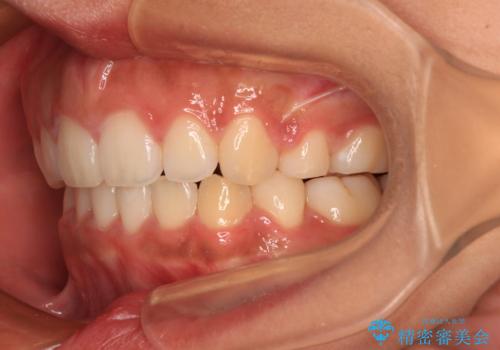

- 出っ歯と口の閉じにくさ、デコボコを気にして来院された患者様です。

口元の突出感を改善するため、上下左右第一小臼歯4本の抜歯を行い、ワイヤー装置による矯正治療を行うこととしました。

舌の突出癖により上下前歯は非接触であり、非常に前方に飛び出している状態でした。

舌のトレーニングをしっかりと行っていただき、口の閉じやすい歯並びに仕上げることができました。